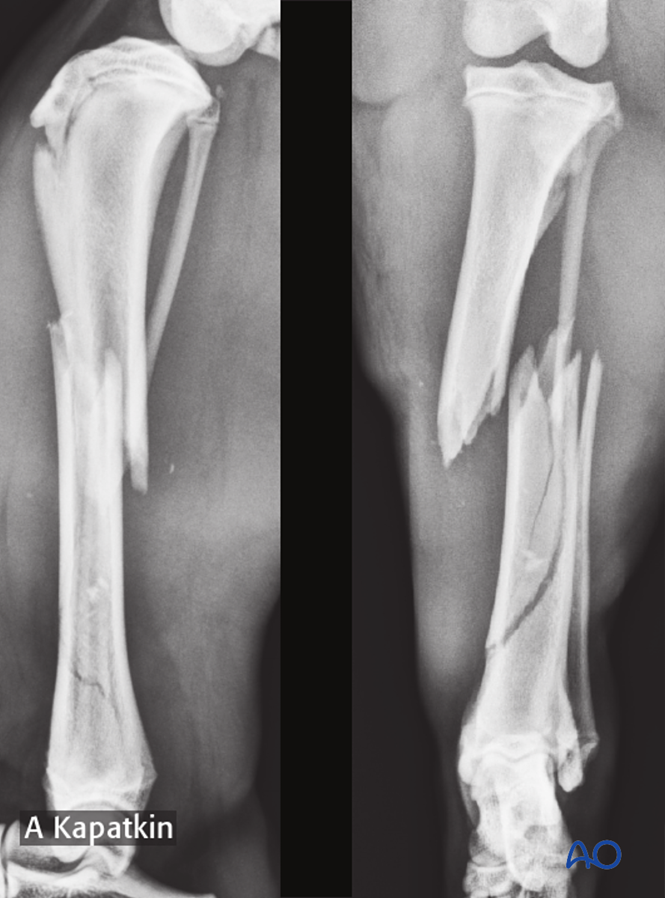

Anterior and lateral radiographic views of the tibia in a child with ...

Tibia And Fibula X Ray X Ray Image Of Tibia And Fibula Fracture. AP